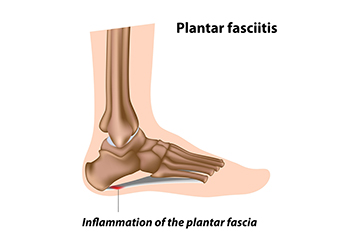

Plantar Fasciitis Causes Heel Pain

One of the most common causes of heel pain is the foot condition that is known as plantar fasciitis. The plantar fascia is a portion of tissue that is found on the sole of the foot. It connects the heel to the toes, and it may become inflamed or torn for various reasons. These can include obesity, standing on hard surfaces for most of the day, or wearing shoes that do not fit correctly. Patients have found the pain may be worse in the morning upon arising, and may feel better as the day progresses. This may be a result of moving the foot, and it is beneficial that specific stretches are performed during the day for continued relief. Additionally, wearing custom-made orthotics may help to reduce existing inflammation and increase comfort level. If you have heel pain, it is suggested that you are under the care of a podiatrist who can effectively diagnose and treat plantar fasciitis.

What Is Plantar Fasciitis?

Plantar fasciitis is one of the most common causes of heel pain. The plantar fascia is a ligament that connects your heel to the front of your foot. When this ligament becomes inflamed, plantar fasciitis is the result. If you have plantar fasciitis you will have a stabbing pain that usually occurs with your first steps in the morning. As the day progresses and you walk around more, this pain will start to disappear, but it will return after long periods of standing or sitting.

Plantar Fasciitis

Plantar fasciitis is one of the most common causes of heel pain. The plantar fascia is the thick band of tissue that connects the heel bone to the toes. When this band of connective tissue becomes inflamed, plantar fasciitis occurs. Fortunately, this condition is treatable.

People with plantar fasciitis often experience a stabbing pain in the heel area. This pain is usually at its worst in the morning, but can also be triggered by periods of standing or sitting. Plantar fasciitis may make it hard to run and walk. It may also make the foot feel stiff and sensitive, which consequently makes walking barefoot difficult.

Treatment for plantar fasciitis depends on the severity of the specific case of the condition. Ice massage applications may be used to reduce pain and inflammation. Physical therapy is often used to treat plantar fasciitis, and this may include stretching exercises. Another treatment option is anti-inflammatory medication, such as ibuprofen.

If you suspect that you have plantar fasciitis, meet with your podiatrist immediately. If left untreated, symptoms may lead to tearing and overstretching of the plantar fascia. The solution is early detection and treatment. Be sure to speak with your podiatrist if you are experiencing heel pain.